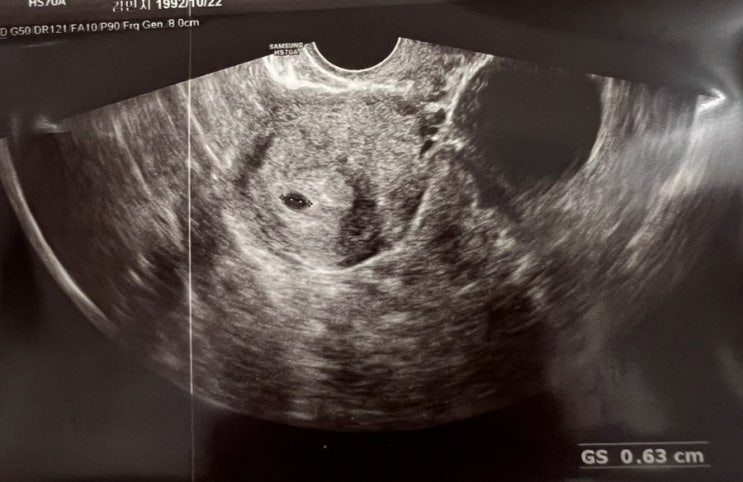

까꿍

임테기 두줄 병원가서 피검사 결과 아직 극초기라 수치가 낮지만(현재수치 23) 임신이 맞다고 함 다음주에 ...